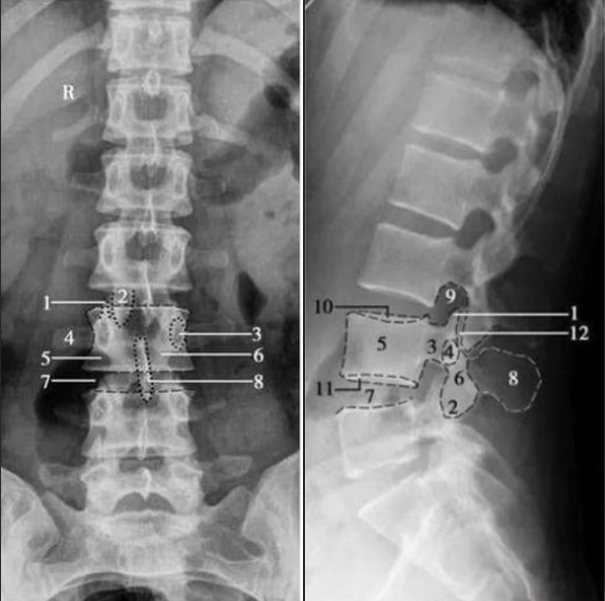

腰椎正側(cè)位

1. 上關(guān)節(jié)突;2. 下關(guān)節(jié)突;3. 椎弓根;4. 橫突;5. 椎體;6. 椎弓板;7. 椎間隙;8. 棘突;9. 椎間孔;10. 椎體上終板;11. 椎體下終板;12. 椎突間關(guān)節(jié)